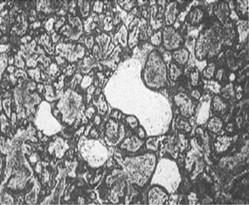

Ameloblastoma menunjukan berbagai macam variasi pola histologi bergantung pada arah dan derajat differensiasi sel tumor. Klasifikasi WHO membagi ameloblastoma secara histologis terdiri dari follikular, pleksiform, acanthomatous, sel granular dan tipe sel basal

- Tipe Folikular

- Menunjukan gambaran histologi yang tipikal dengan adanya sarang-sarang folikular dari sel tumor yang terdiri dari lapisan dan sebuah massa sentral yang menyerupai retikulum stellata.

- Degenerasi dari jaringan yang berbentuk seperti reticulum stellata itu akan menghasilkan pembentukan kista.